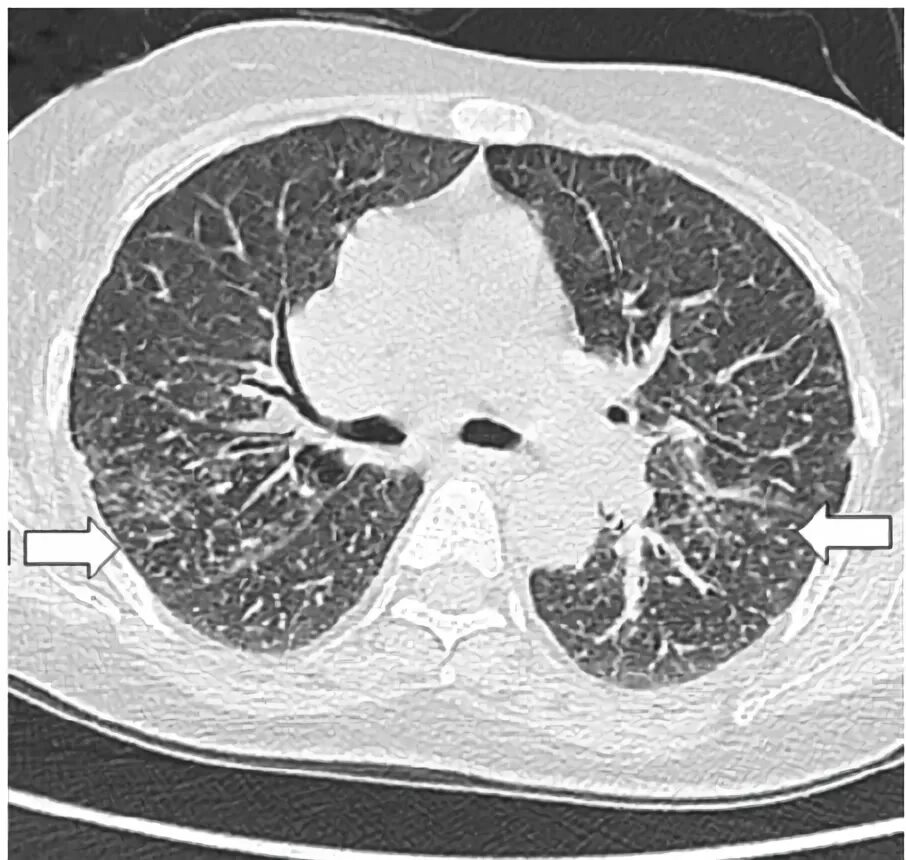

Фиброз кт